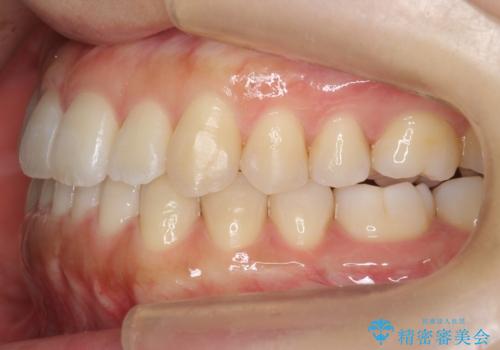

奥歯のかみ合わせの前後的なずれをそのままにして治療すると、前歯が突き上げるような状態になってしまいます。

ただその場で並べるのではなく、症状によっては奥歯を後ろに下げる必要があります。